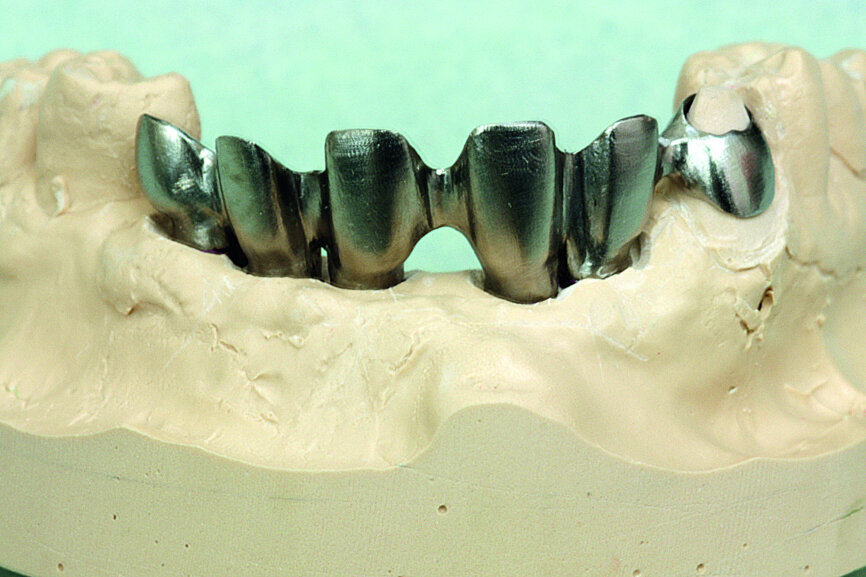

Fig. 32: Final prosthesis framework and the coping for the right canine tested on the working model.

Fig. 33: Final prosthesis framework and the coping for the right canine tested on the working model.

This prosthesis serves as a model for the final prosthesis. It is made with easily modifiable material like resin, but with a metal framework to guarantee a certain level of rigidity. In the first step, a model of the framework, which temporarily included the canine to increase stability, was cast in pattern resin (Fig. 21). The model was then scanned (Aadva, GC Tech.Europe; two cameras, 2 MP, precision: 10 μm) before being transferred to a machining centre (GM 1000, GC Tech.Europe; Figs. 22–24). Once back from the machining, the titanium framework was tested on the working model and its stability was verified (Figs. 25 & 26).

The cosmetic material (UNIFAST III resin; surface rendering: OPTIGLAZE color, GC Tech.Europe) was then placed on the framework (Fig. 27). The bone graft permitted a maximum reduction of the vestibular false gingiva.